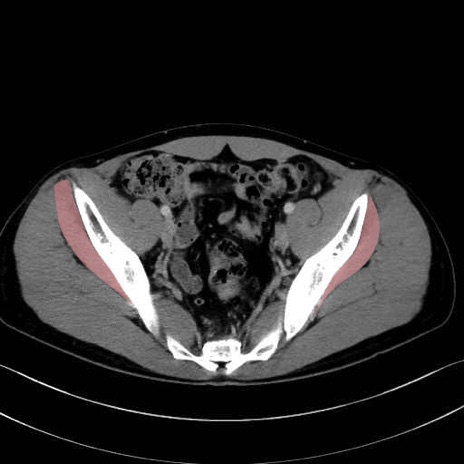

小殿筋 (Gluteus minimus)